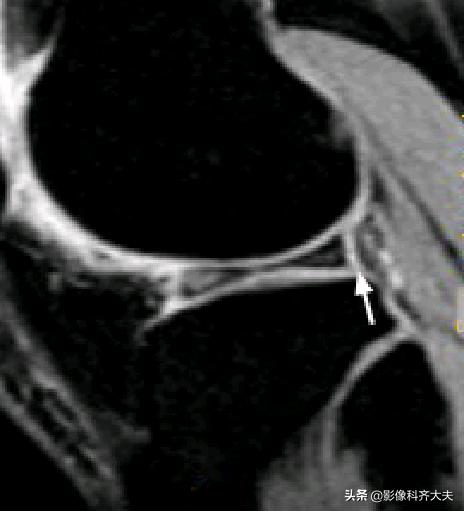

后股板韧带: